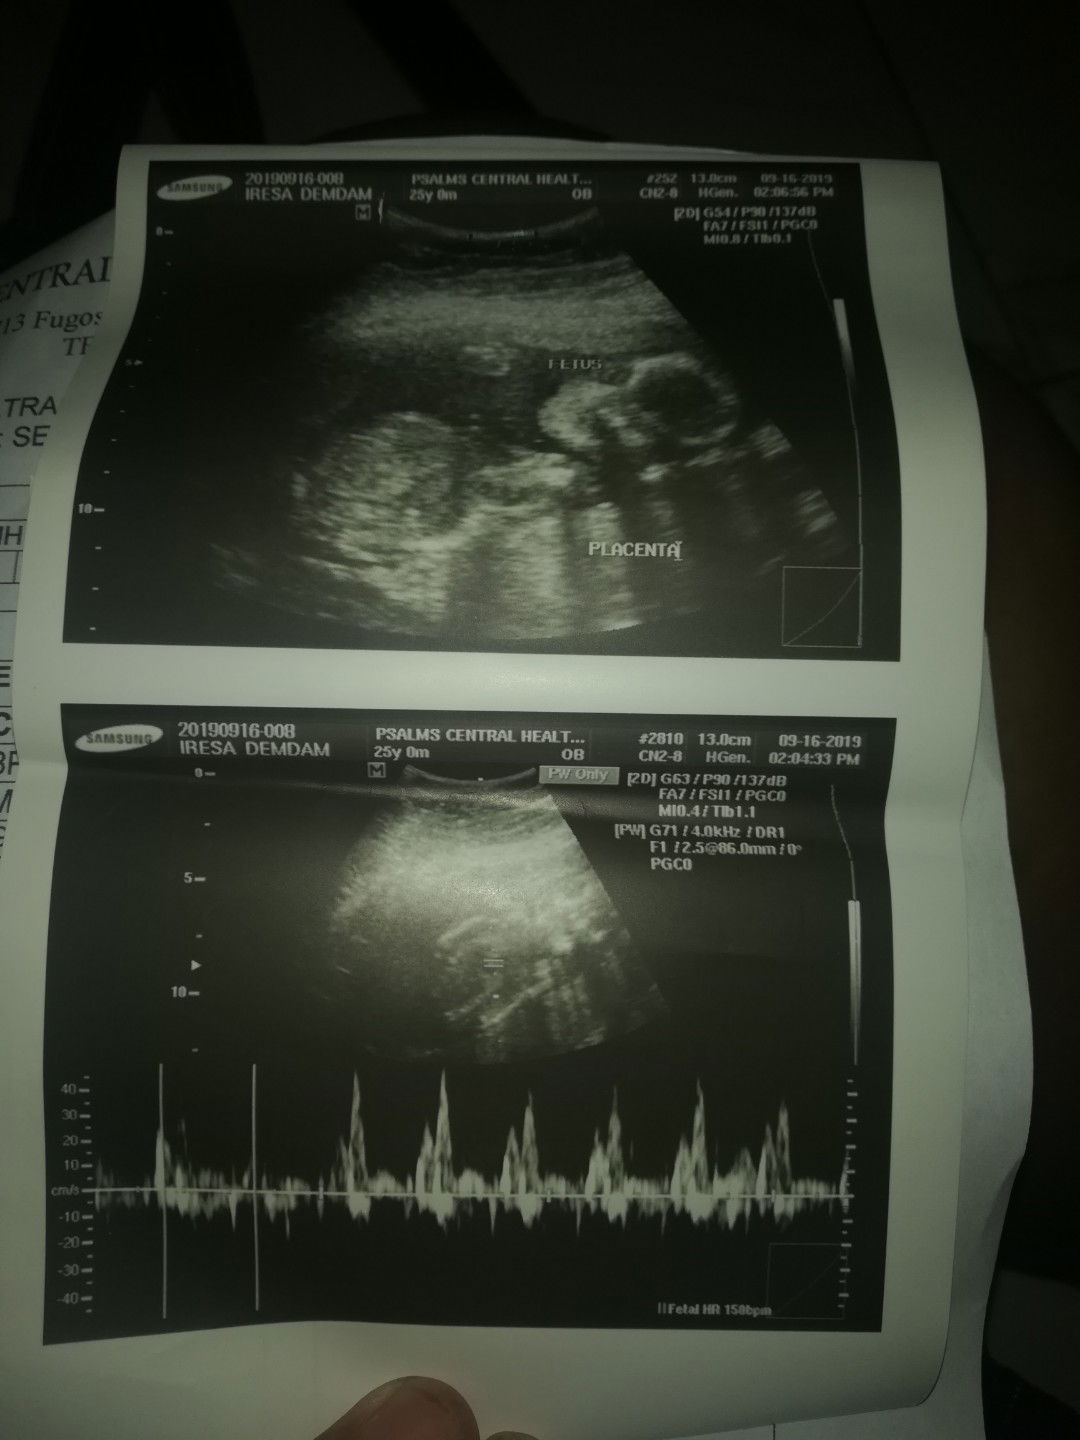

18weeks ?

nag paultrasound ako kanina para sana malaman gender ni baby. pero hindi nilagay ni doc. :( nung tinanung ko sya okay naman daw si baby , i ask the gender din sabi nya tingin nya baby girl kase daw wala syang nakikitang lawit ? bb girl na nga sana hehehe my same ultrasound po ba ko dto ? ?